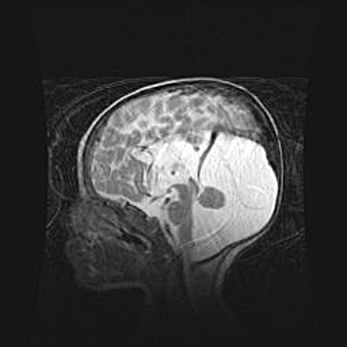

Аномалия Денди-Уокера. Признаки гипоплазии мозолистого тела.

Возраст: 5 месяцев 3 дня

Вес: 5550 г

Пол: мужской

Окружность головы: 39 см

Срок гестации: 40 недель

Аномалия Денди-Уокера – это порок развития головного мозга, для которого характерна триада симптомов: гипотрофия или аплазия червя мозжечка и/или полушарий мозжечка, расширение четвёртого желудочка с формированием ликворной кисты задней черепной ямки, гипертензионная гидроцефалия различной степени.

Гипоплазия мозолистого тела относится к дефектам внутриутробного этапа развития мозговой ткани, возникающим в процессе закладки структур головного мозга, что происходит на начальных этапах развития эмбриона.